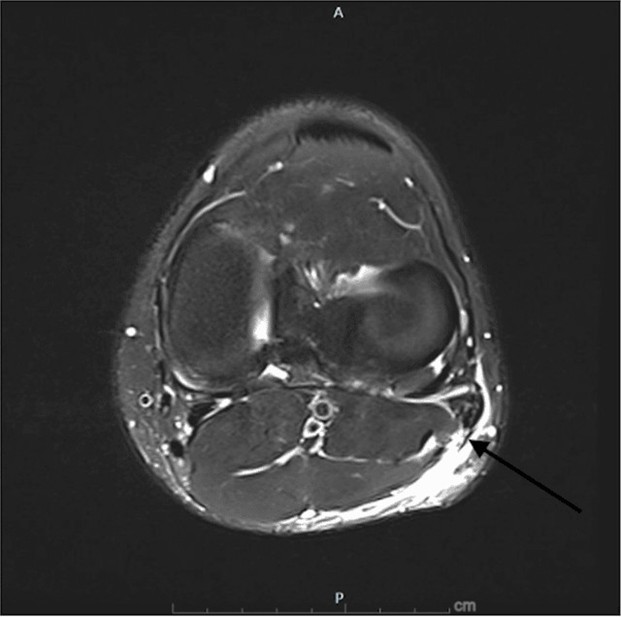

Given the clinical findings, an MRI of the left knee was obtained the same day, shown in Figures 1-3. Imaging revealed a near-complete tear of the distal biceps femoris tendon at the musculotendinous junction, approximately 5 cm proximal to its fibular insertion. Importantly, the tendon remained in continuity with the fibular head, with no frank avulsion. The lateral collateral ligament and posterolateral corner structures appeared intact [7].

Figure 2. MRI (axial view) of initial injury. The arrow is pointing to edema within the tendon sheath, signifying a high-grade/complete tear of the distal biceps femoris tendon.